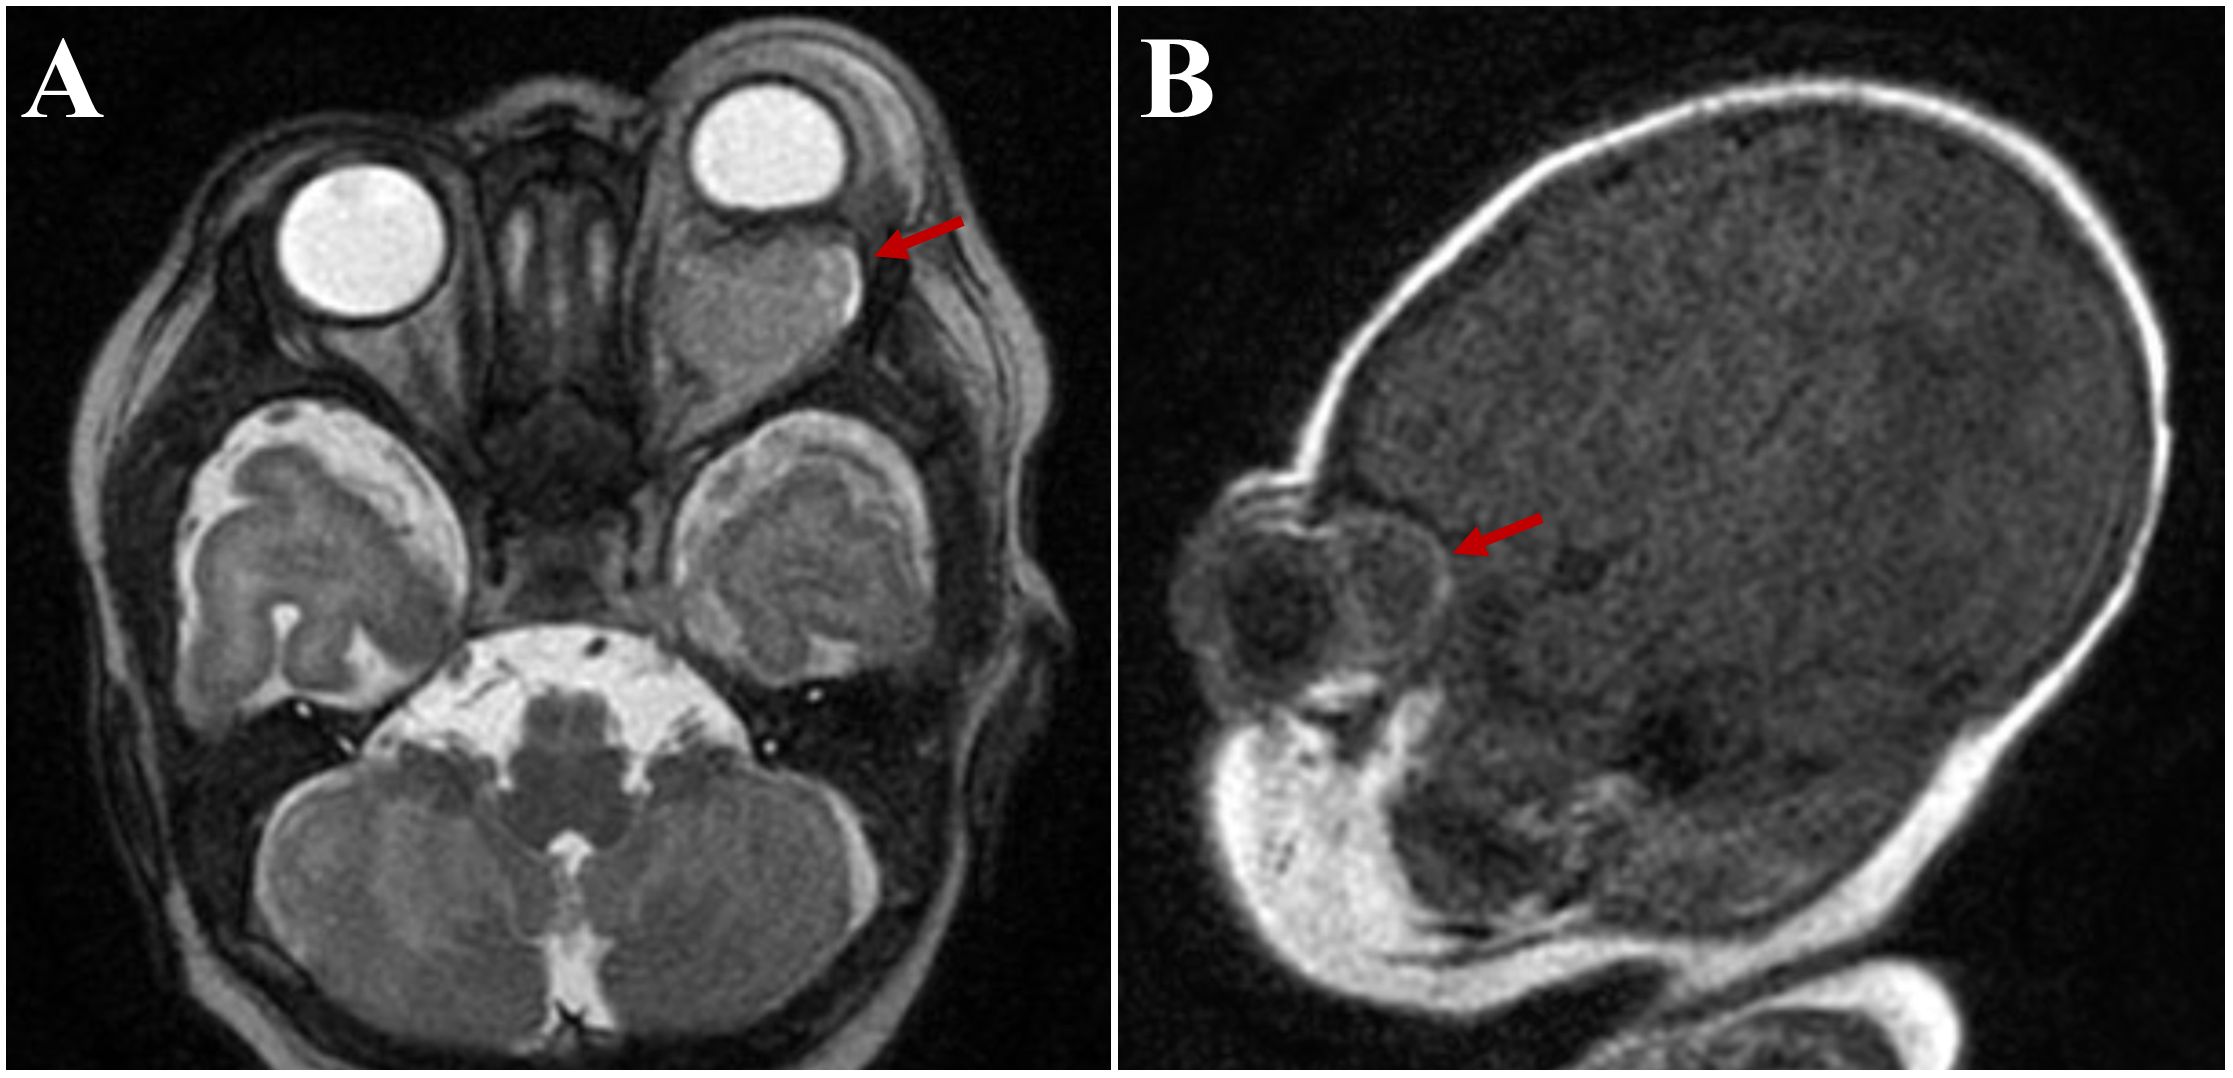

Magnetic resonance imaging (MRI) was obtained to rule out abscess. It showed a 1.5x1.9x2.1 cm left intraconal mass with significant mass effect displacing the optic nerve and 9 mm of proptosis. Diffuse pre-septal soft tissue edema was also noted (Figure 2). This was initially interpreted by the reading radiologist as an abscess, however consultation with the orbital surgeon raised concerns for cystic mass such as lymphatic malformation or teratoma.

Figure 2. Axial (A) and sagittal (B) magnetic resonance images, demonstrating a 1.5x1.9x2.1 cm left intraconal mass initially read as “abscess” (arrows).